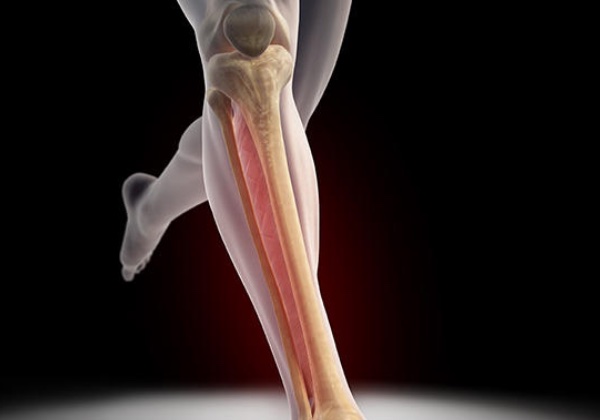

Kas ve tendonun kemiğe bağlanma yerinin inflamasyonudur. Kemik tendon bölgesinin kanlanması buradaki fibrokartilaj dokunun bariyer oluşturması nedeniyle iyi değildir. Bu nedenle bu bölgede gelişen zedelenmelerin iyileşmesi uzun sürmekte ve sıklıkla kronikleşmektedir. Kemik tendon yapışma yerinin tekrarlayan mikrotravmaları sonucu oluşur. Tekrarlayan mikrotravmalar kısmi yırtıklara ve kanamalara neden olur. Bu bölgede irritasyon ve inflamasyon oluşur. Büyüme çağındaki kişilerde tenoperiostit daha nadir görülmaktedir. Çünki bu bireylerin tendon ve kasları kemiğe oranla daha kuvvetlidir. Hatta os goog schlatter ve calcaneal apofizitte olduğu gibi inflamasyon devam eder ve kemikte fragmantasyona yol açabilir. Tenoperiostit sıklıkla, dirsek bölgesinde (tenisci dirseği, golfcü dirseği), kasıkta adduktor longusun yapışma yerinde, dizde patellar tendonun proksimal ve distal bağlantı bölgelerinde, aşil tendonunun kalkaneusa bağlanma yerinde ve plantar fasianın kalkaneusa bağlanma yerinde (plantar fassiit) oluşabilmektedir. Tendon ve kasın kemiğe yapışma yerinde ağrı, hafif şişlik, fonksiyonda bir miktar kayıp, yapışma yerine hafif bası ile hassasiyet, ilgili kas grubunun kasılması ile yapışma yerinde ağrının artması ile karekterize şikayetler mevcuttur.